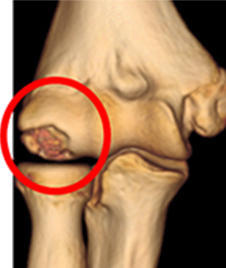

離断性骨軟骨炎の画像

肘の外側

(3D-CT)

離断性骨軟骨炎